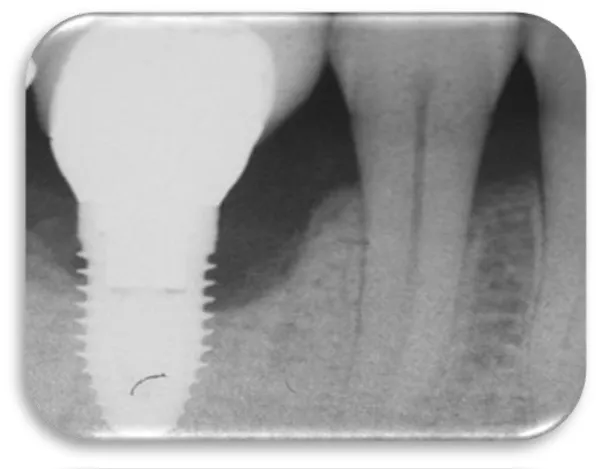

The tenth clinical case was a 30 year old female patient. Before a period of 7 months she received dental implant due to a missing of the frontal right central incision 11. The patient was in excellent health and without allergy to any medication. An X-ray was made, showing changes in bone tissue around the dental implant. Around dental implant (from the mesial and distal side) a bone defect was detected, which occurred after a period of seven months. During the probing around the dental implant, the probe went down 4 mm in pocket from the mesial side and 3 mm from the distal side. The greater loss of bone tissue was detected from the mesial side of the dental implant than from the distal side. The patient was identified to have peri-implant disease (Figure 34).